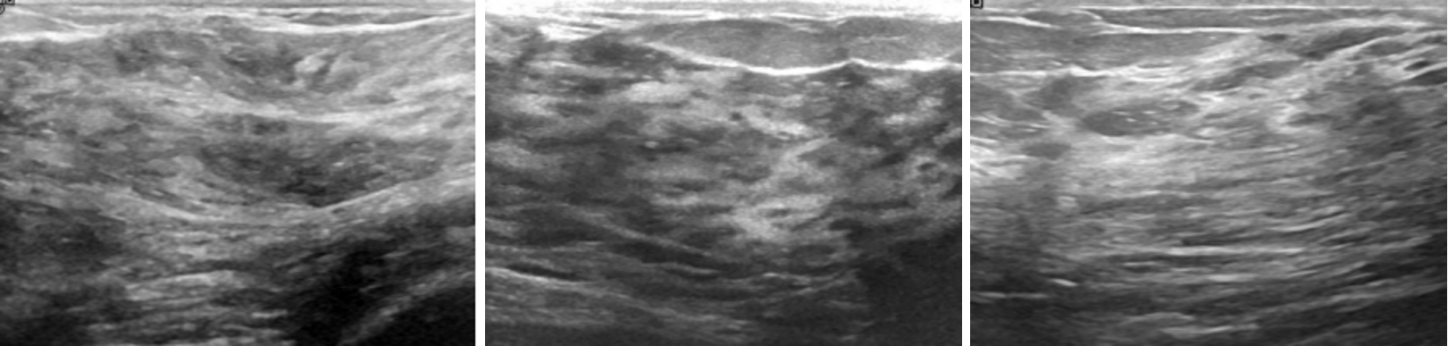

The experimental data for this study was sourced from the Breast Ultrasound Images Dataset on the Kaggle platform. This open-source dataset comprises 780 breast ultrasound images collected in 2018 from 600 female patients aged 25 to 75. The images are in PNG format with an average size of 500×500 pixels and include ground truth labels categorised into three classes: normal, benign, and malignant. For binary classification, this study categorises the images into two groups: "non-diseased" (normal) and "diseased" (benign + malignant) ( Figure 2,3).